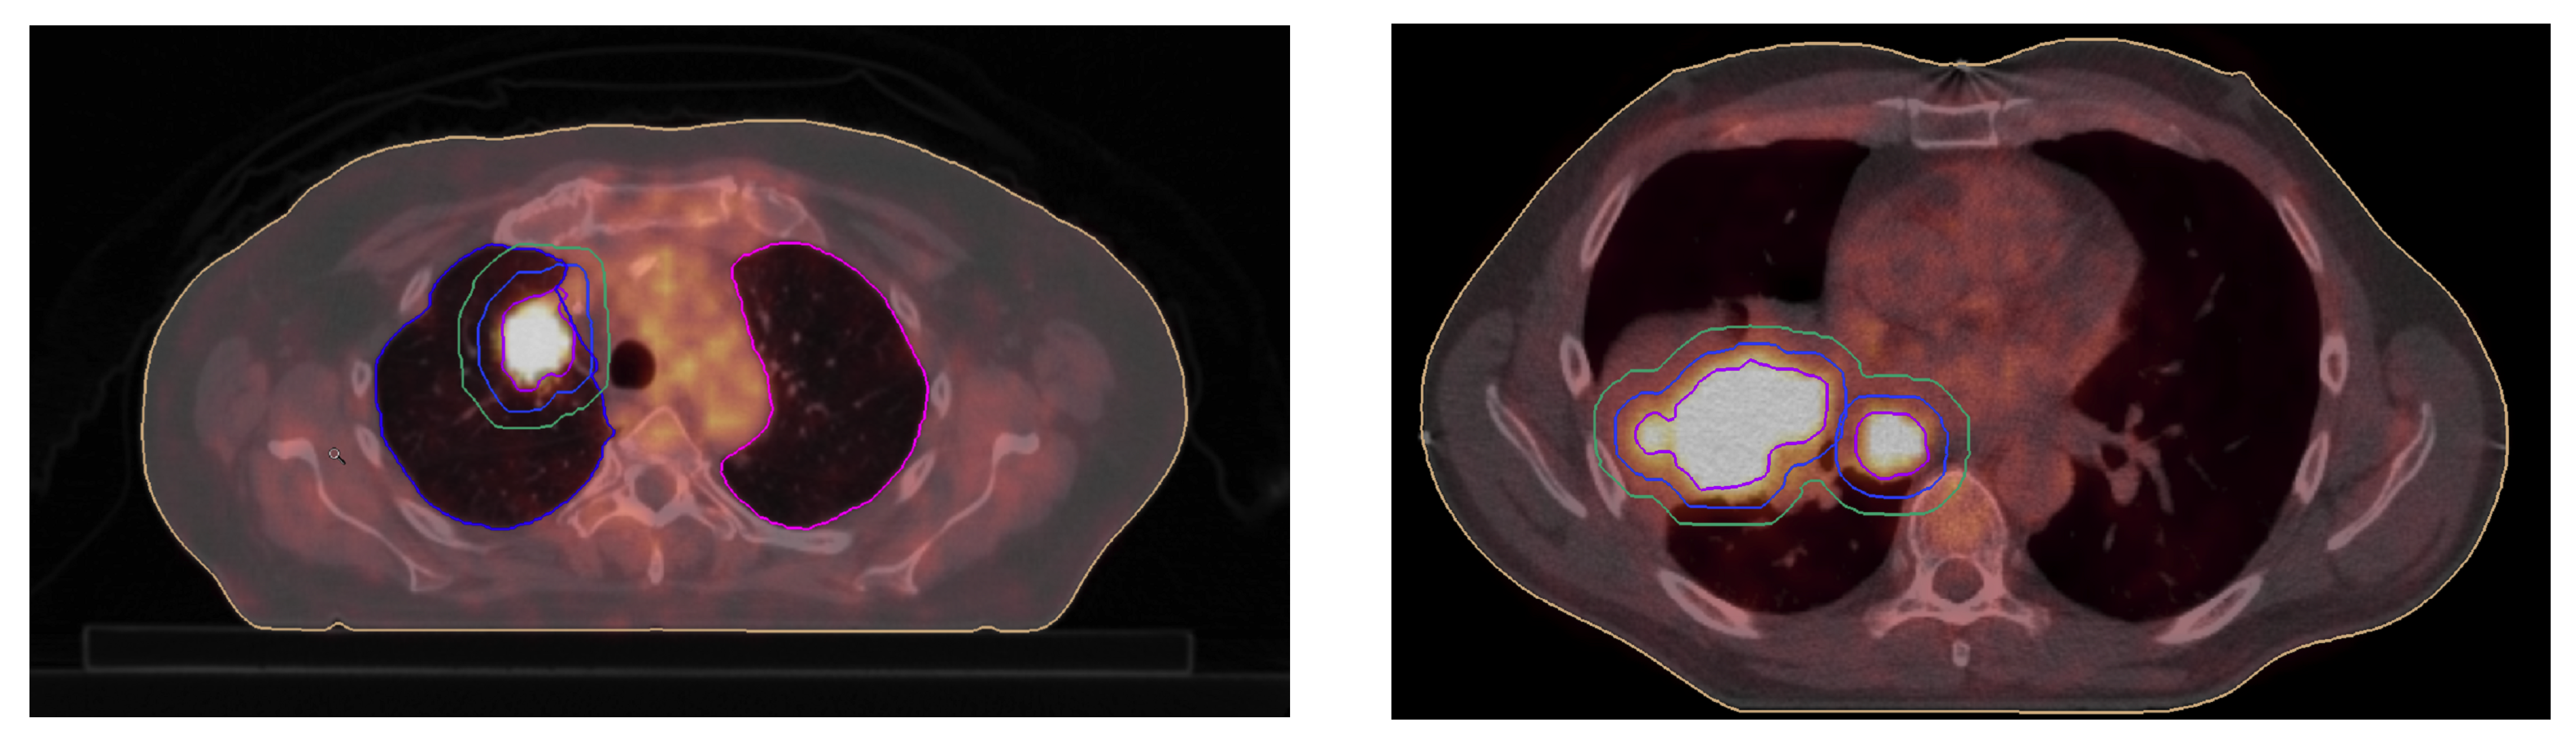

5. Illustrations